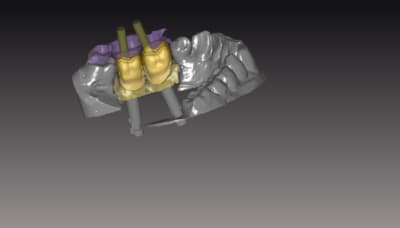

exemple de réalisation ..

sur ce cas pas de base titan, pas nécessaire because branemark , exagone externe base large ,bonne surface d'assise

Je posterais d autre cas sur du nobel activ (avec ambase ) strauman BL et NBreplace

faites l'économie d'un pilier , et appréciez le confort du transvissé :):)

_l_ments_termin_s_avant_usinage_ora1mc.png

sans_gencive_eg5noe.png

vue_V_apr_s_r_duction_copie_iuwrrb.png

VueL_apr_s_r_duction_copie_oi1z1z.png

VueL_apr_s_r_duction_bb7js4.png

L_sans_gencive_r0aytd.png

vue_chemin_e_occ_adapt_e_a_la_morphologie_e0mxr3.png

Vue_Emergence_uvtieo.png

vue_V_apr_s_r_duction_lzpmal.png

VueOc_hrkdso.png

VueV_vptbye.png